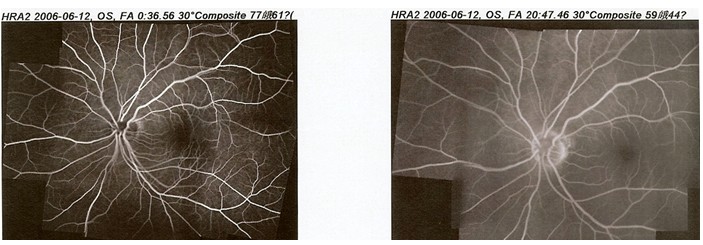

眼底荧光血管造影检查FFA(Fundus fluorescein angiography)

【功 能】:使用共焦激光扫描技术,通过造影剂显示血管走行情况、血管形态变化情况、血管充盈与渗漏情况,综合上述三种情况对眼底病变作出诊断。

【适应症】:主要了解眼底血管血液供应的情况,临床上多用于缺血性病变、血管阻塞、新生血管的发现、眼内肿瘤血管充盈的情况等病变的检查。